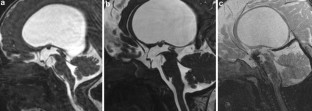

Fig. 1